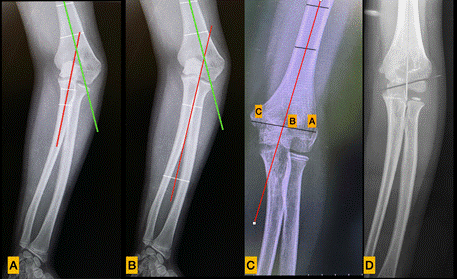

Son múltiples los criterios de evaluación clínicos y radiográficos encontrados en la bibliografía para de medir las deformidades a nivel del codo (Imagen 1). Oppenheim en 1984 describe el humeral-elbow-wrist angle (HEW) para evaluar los resultados postoperatorios en las osteotomías del humero distal 15. Recientemente este ángulo fue validado como una medida fiable de la alineación en el plano coronal del humero y del antebrazo. El mismo se traza mediante una primera línea a nivel de la diáfisis humeral y una segunda línea perpendicular a dos puntos medios transversales que cruzan el antebrazo. La línea proximal se traza al nivel de la tuberosidad radial y la distal en la curvatura del radial. Un valor negativo indica varo, mientras que un valor positivo indica valgo 16.

El ángulo de carga es un ángulo formado entre el eje longitudinal del humero y una segunda línea que pasa a través del eje longitudinal del cubito. La línea diafisaria cubital pasa por el centro de dos líneas transversas. La línea proximal se traza a nivel del olecranon y la distal se traza a nivel de la tuberosidad bicipital 17.

El Índice de Prominencia Lateral (LCPI) descrito por Wong et at valora la prominencia del cóndilo trazando una línea medio humeral longitudinal, midiendo de esta forma la diferencia del ancho del lado medial y lateral. El resultado se expresa en porcentaje. (Imagen 1) 19